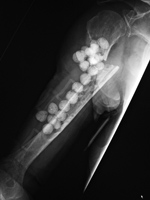

36 year-old man with loss of index finger and a portion of the third metacarpal from a gunshot wound. The antibiotic laden cement block is stabilized by a small malleable plate and screws for treatment of third metacarpal bone infection. |